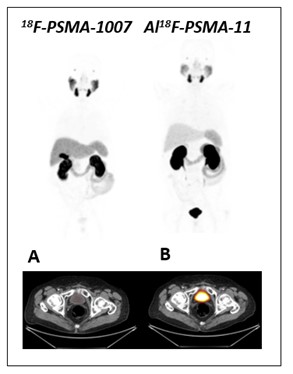

Figure 1: Normal biodistribution of 18F-PSMA-1007 and 18F-AlF-PSMA-11. MIP and axial PET/CT images of a prostate cancer patient showing no urinary excretion of 18F-PSMA-1007 (A) that enables excellent assessment of the prostate. Note that increasing accumulation in gallbladder and in the liver could limit the detection of unusual liver metastases). Besides, normal accumulation of 18F-AlF-PSMA in the urinary bladder (B) difficult interpretation.